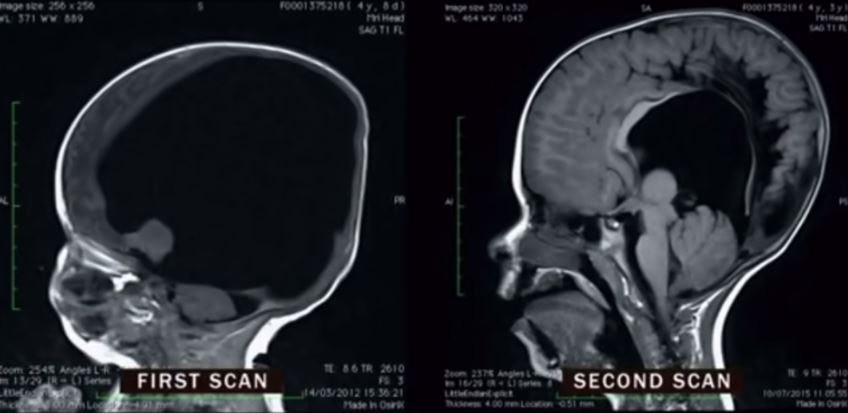

能成功健康孕育一個小朋友絕對唔係必然,當發現肚內BB唔健康,被醫生建議終止懷孕時,相信會係做媽媽人生最難決定嘅事。英國有位媽媽懷孕3個月時,被檢查發現BB發育異樣,包括脊柱裂、染色體異常、腦積水,甚至大腦發育只有2%。

幸運地,之後能夠遠赴澳洲接受神經物理治療,透過物理治療同訓練認知能力,Noah學識坐起身,到咗3歲時,Noah腦部發展奇蹟達到正常嘅80%。宜家6歲嘅Noah發展逐漸正常,下個終極目標係可以行路,同學識滑浪。

醫生都無法解釋Noah嘅情況,形容病例係奇蹟。有人認為Noah可能一開始只係因為大腦集中一邊,導致發育異常,但後來成功移回正常位置發育;但根據依嗰假設,Noah應係重度智障患者,唔可能好似宜家咁聰明,但唯一可以肯定係,Noah證明大腦修復神經系統方面係有驚人潛能,為腦部受損患者帶嚟新希望。